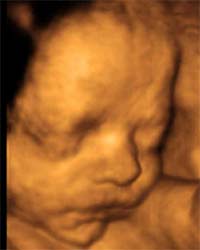

¡Conoce cómo es tu bebé y cómo se mueve antes de que nazca! La evolución de la ciencia es continua y la ecografía 3D con movimiento, la llamada ecografía 4D se está convirtiendo cada vez en algo …